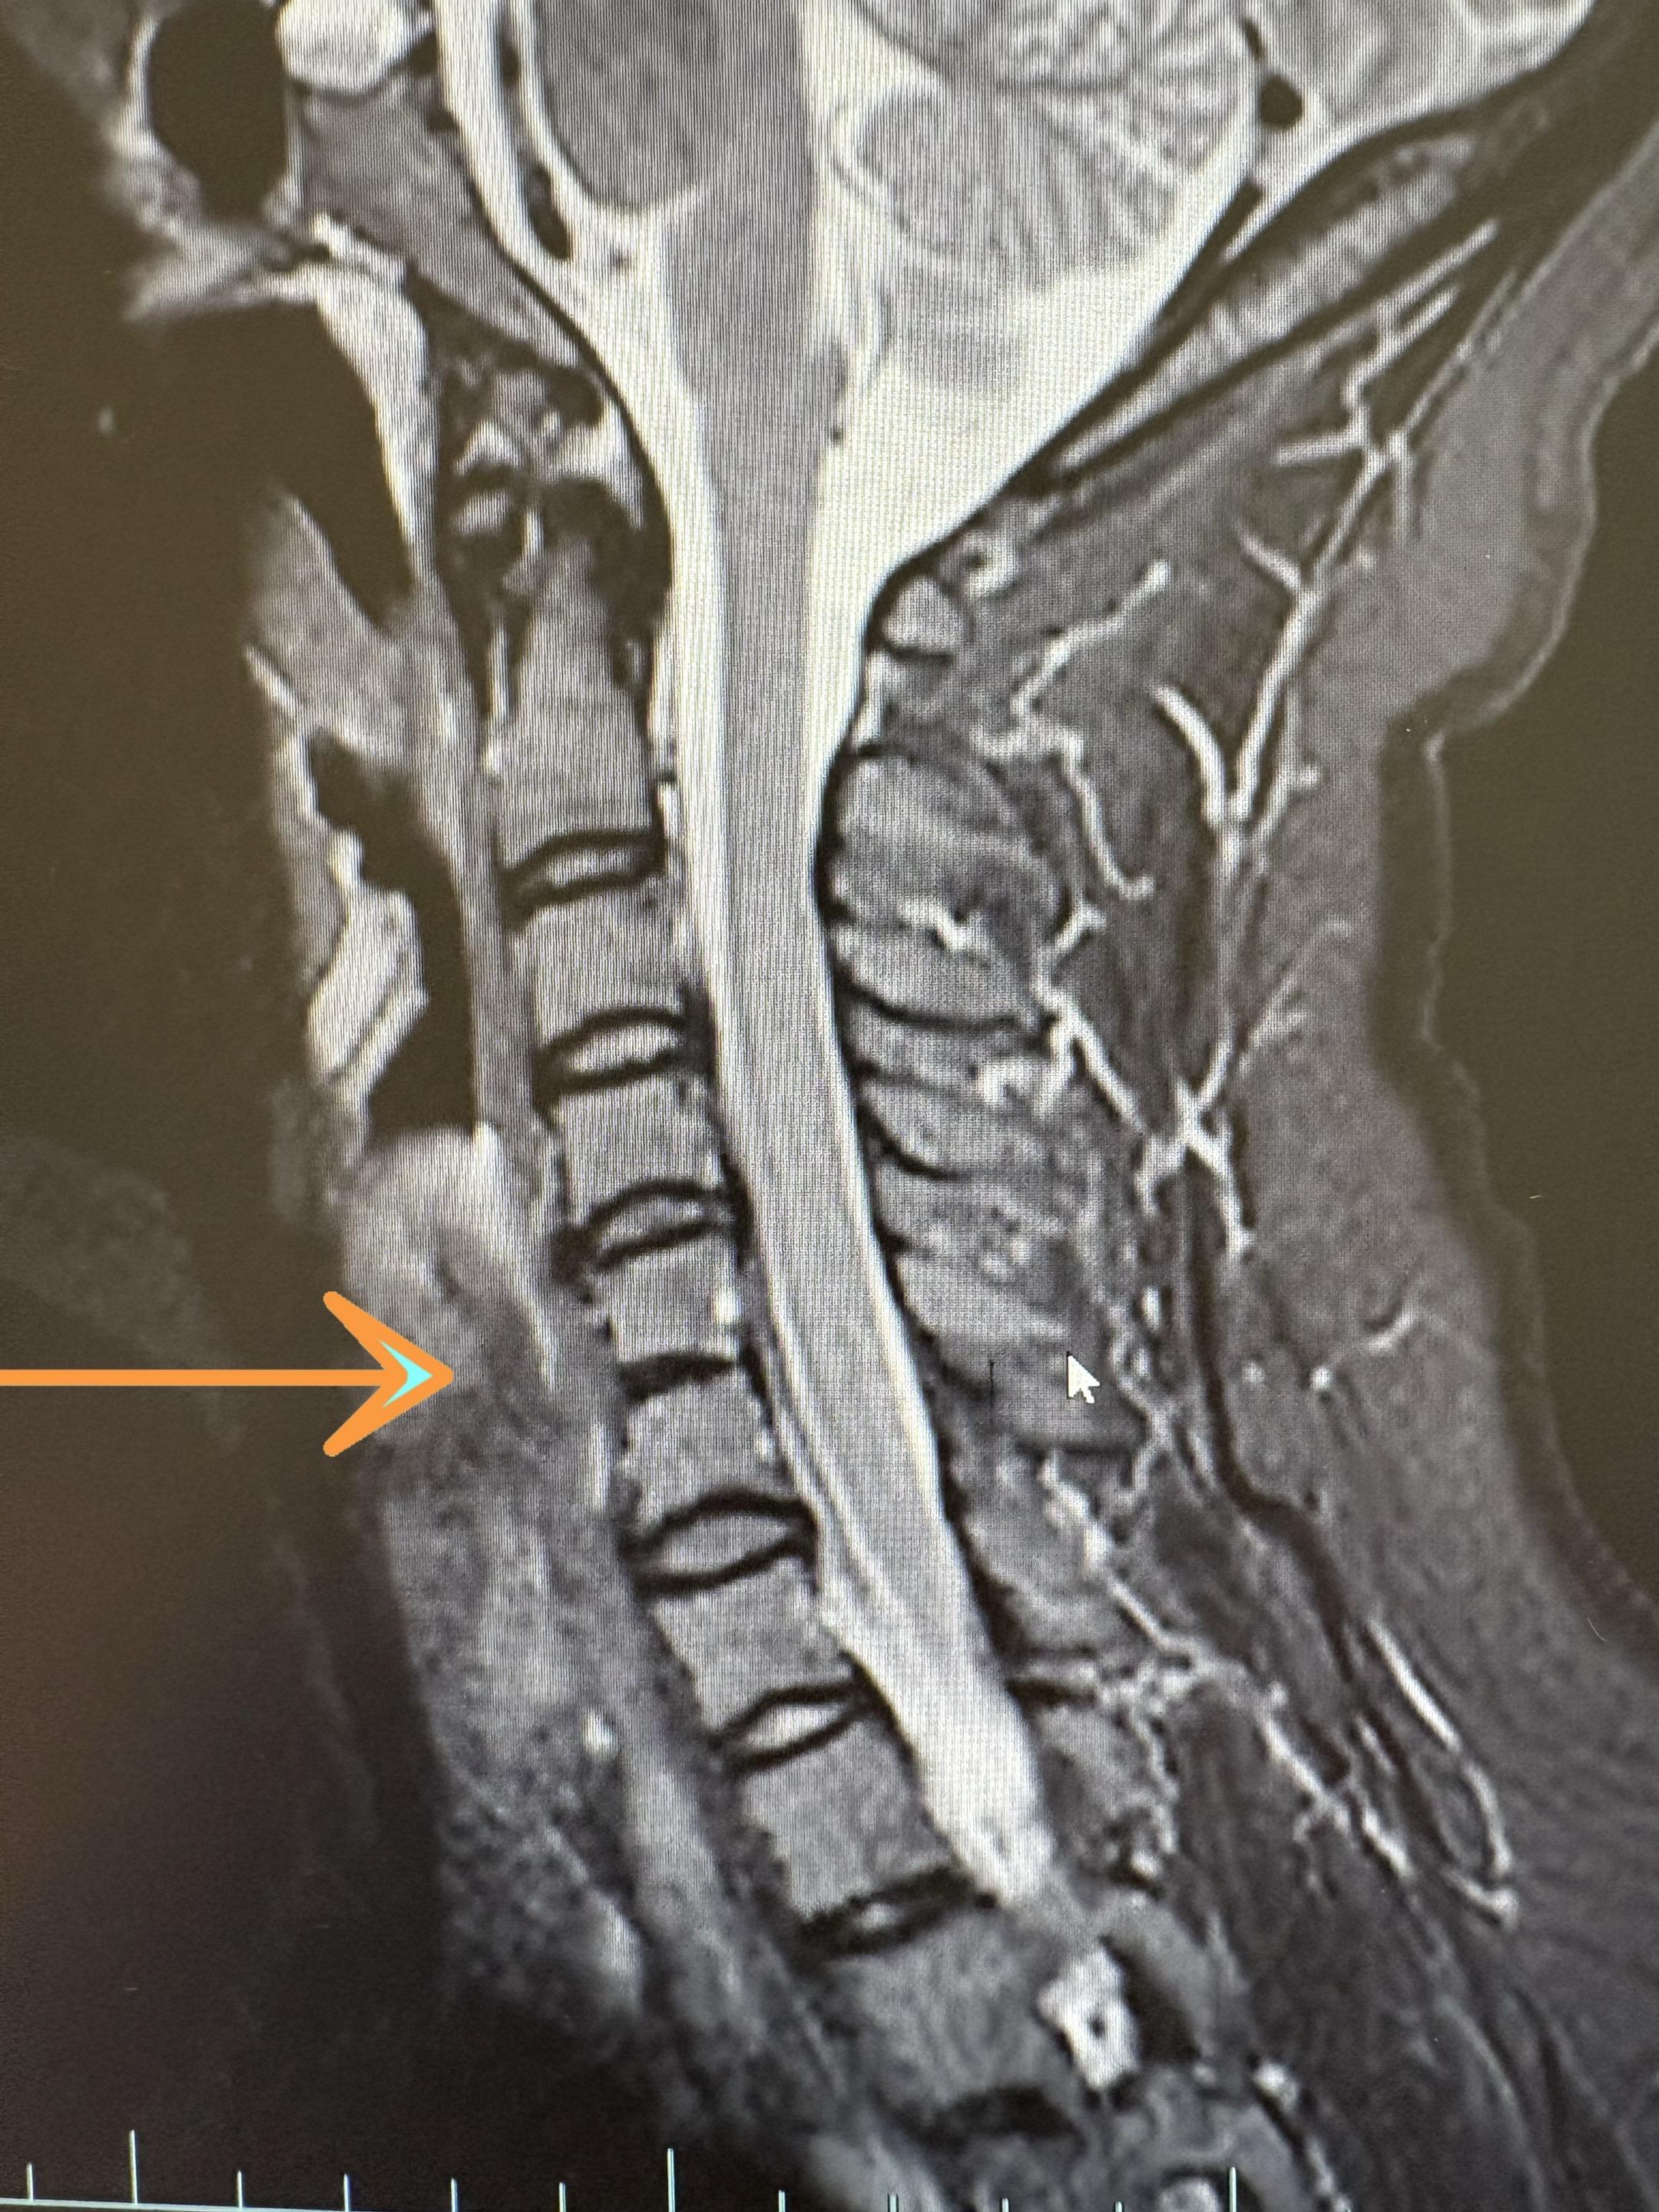

颈56椎体分节不全。一种常见的颈椎发育畸形 klippel-feil综合征

颈56椎体分节不全。一种常见的颈椎发育畸形医学影像 颈椎病 klippel-feil综合征